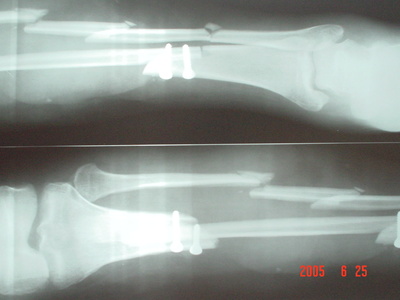

微创骨科经典病例

腓骨创伤移植修复